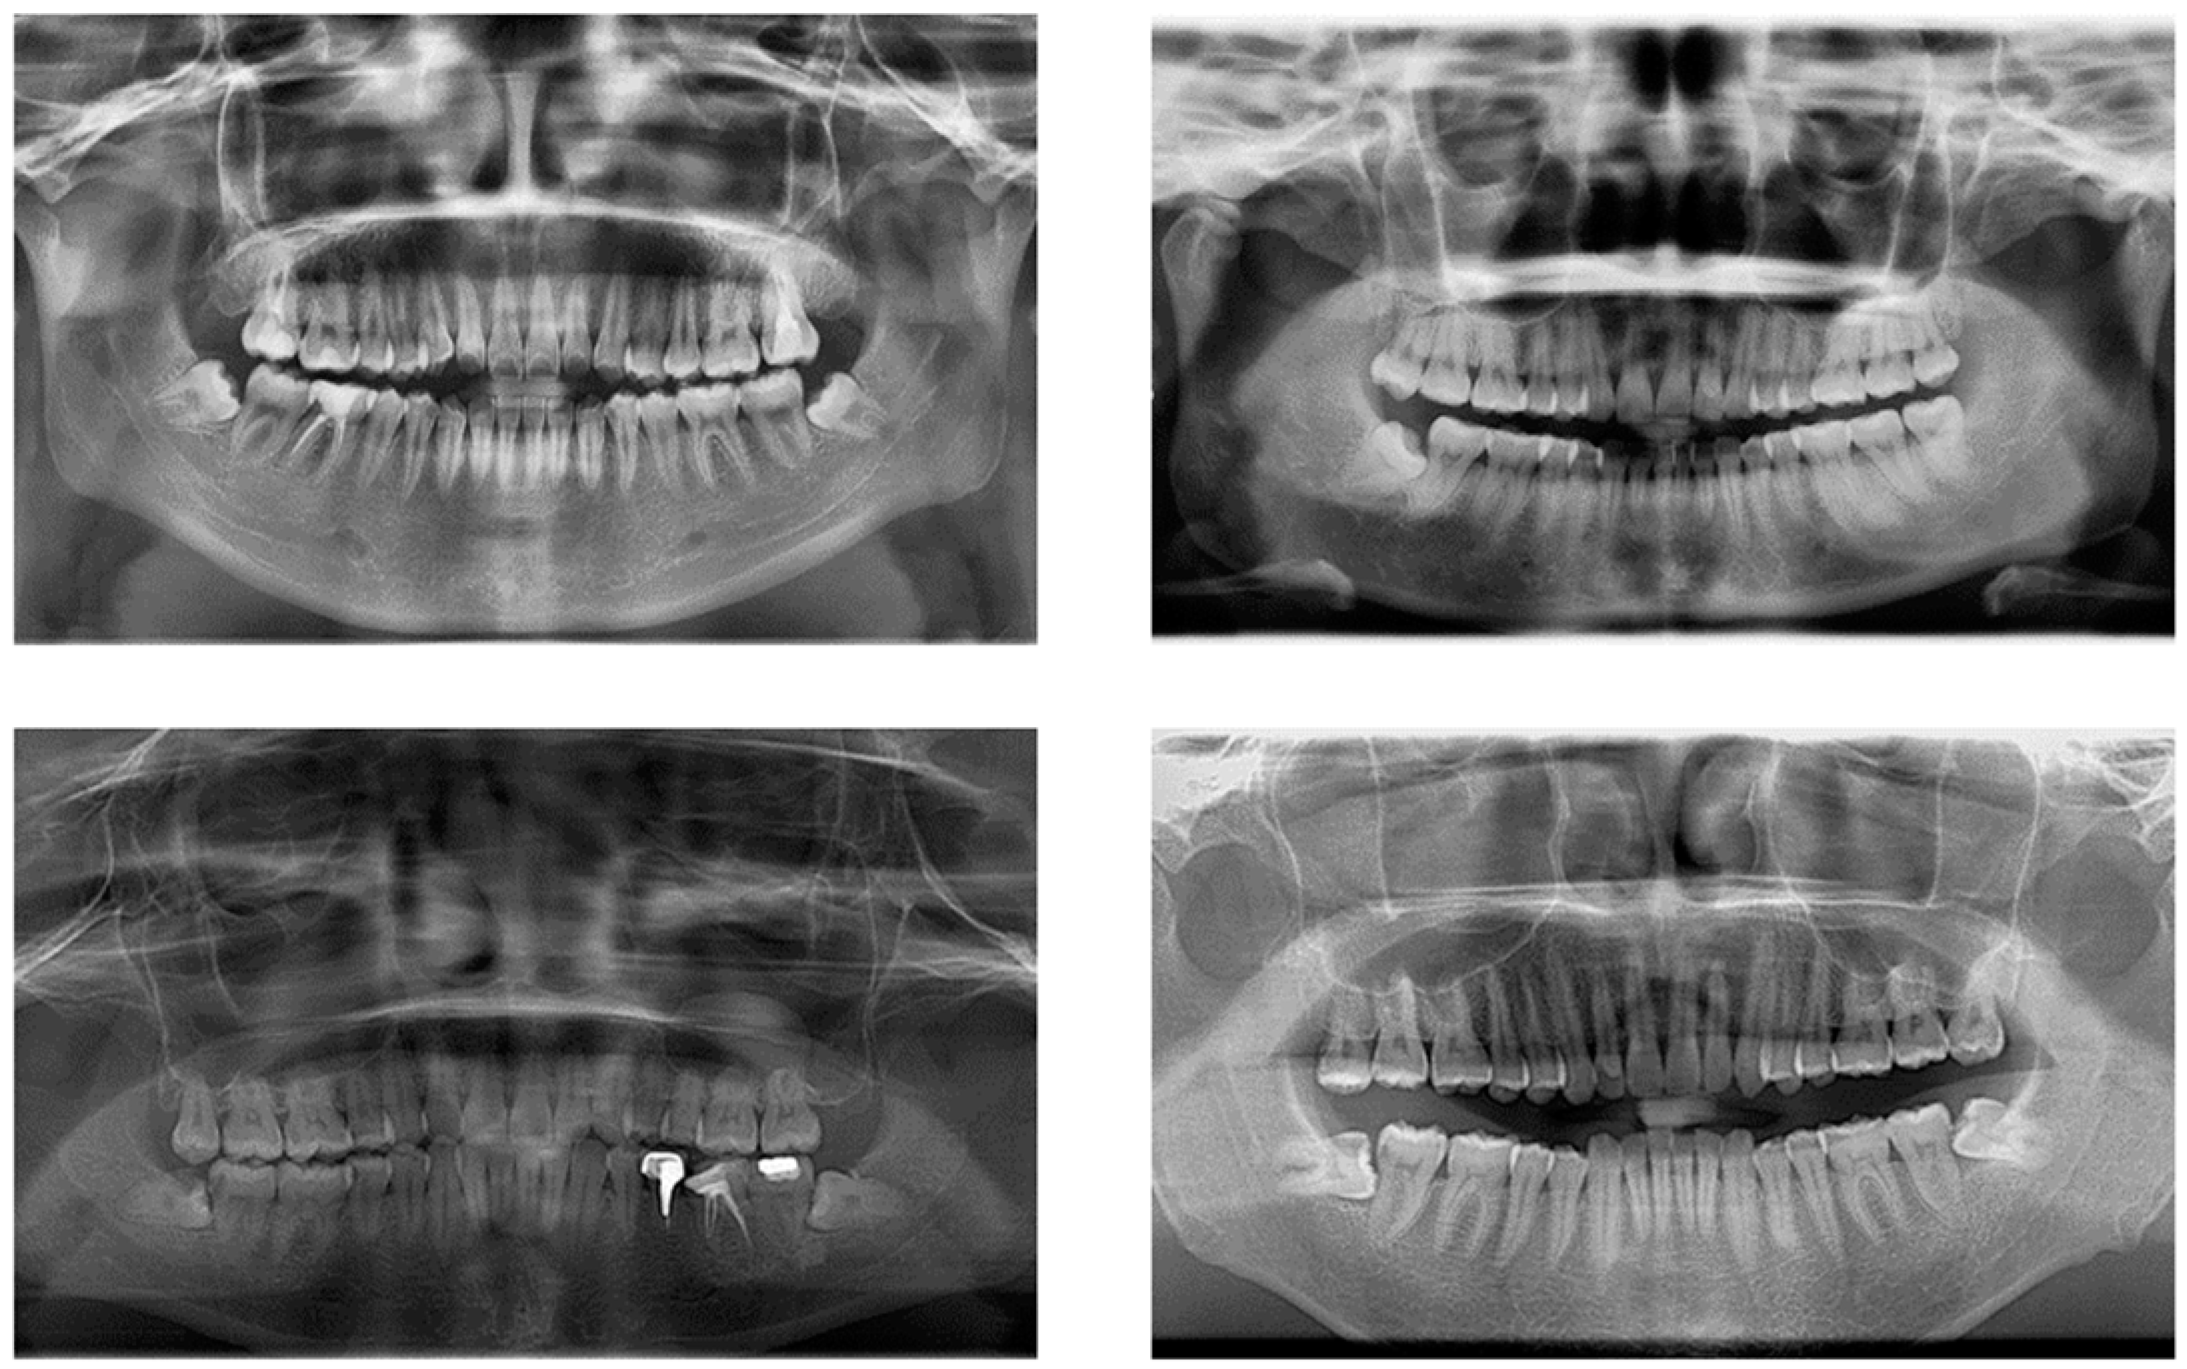

The impacted mandibular third molar dataset constructed for this study came from the School of Stomatology, Lanzhou University, with 2146 images; all the images were collected by Gendex Orthoralix 9200 DDE panoramic X-ray machine. After removing panoramic radiographs with artefacts, underdeveloped roots (which mean that the apical foramen has not been completely closed), and distorted positions, 1347 qualified images were finally obtained. The original images were in DCM format, and we used Python to convert them to JPG format; the size of the converted image is 2720 × 1444, and the converted images are shown in Figure 1.

Figure 1. Example images of the dataset.